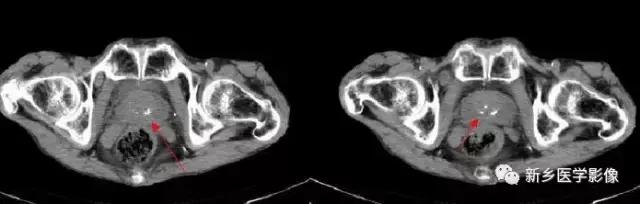

9、输精管钙化

主要表现为盆腔内对称性小钙化灶。